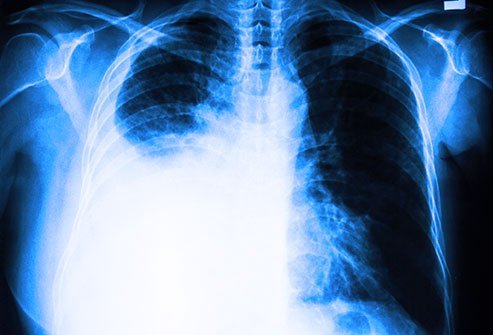

Chest X-ray can detect pleural effusions, as they usually appear as whitish areas at the lung base, and they may occur on only one side (unilateral) or on both sides (bilateral). If a person lies on their side for a few minutes, most pleural effusions will move and layer out along that side of the chest cavity which is positioned downward (because of the effects of gravity). This movement of the pleural effusion can be seen on a chest X-ray taken with the person lying on their side (a lateral decubitus X-ray).